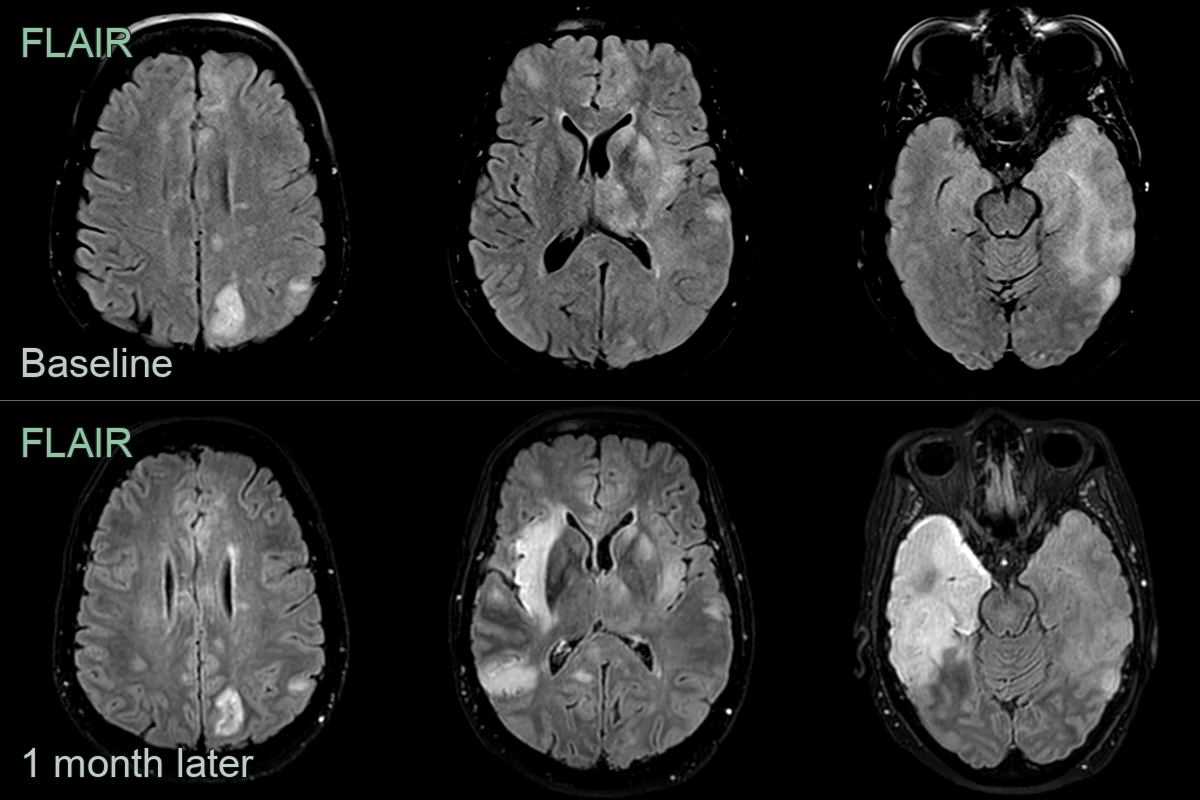

• 60-year-old patient presented with expressive dysphasia.

• MRI showed diffuse patchy cortical, white matter and ganglionic hyperintensity.

• On follow-up, hyperintensity involving most of the left temporal lobe resolved while marked hyperintensity developed in the right temporal lobe.

• Despite being repeatly negative on CSF, brain biopsy reavealed an HSV encephalitis.